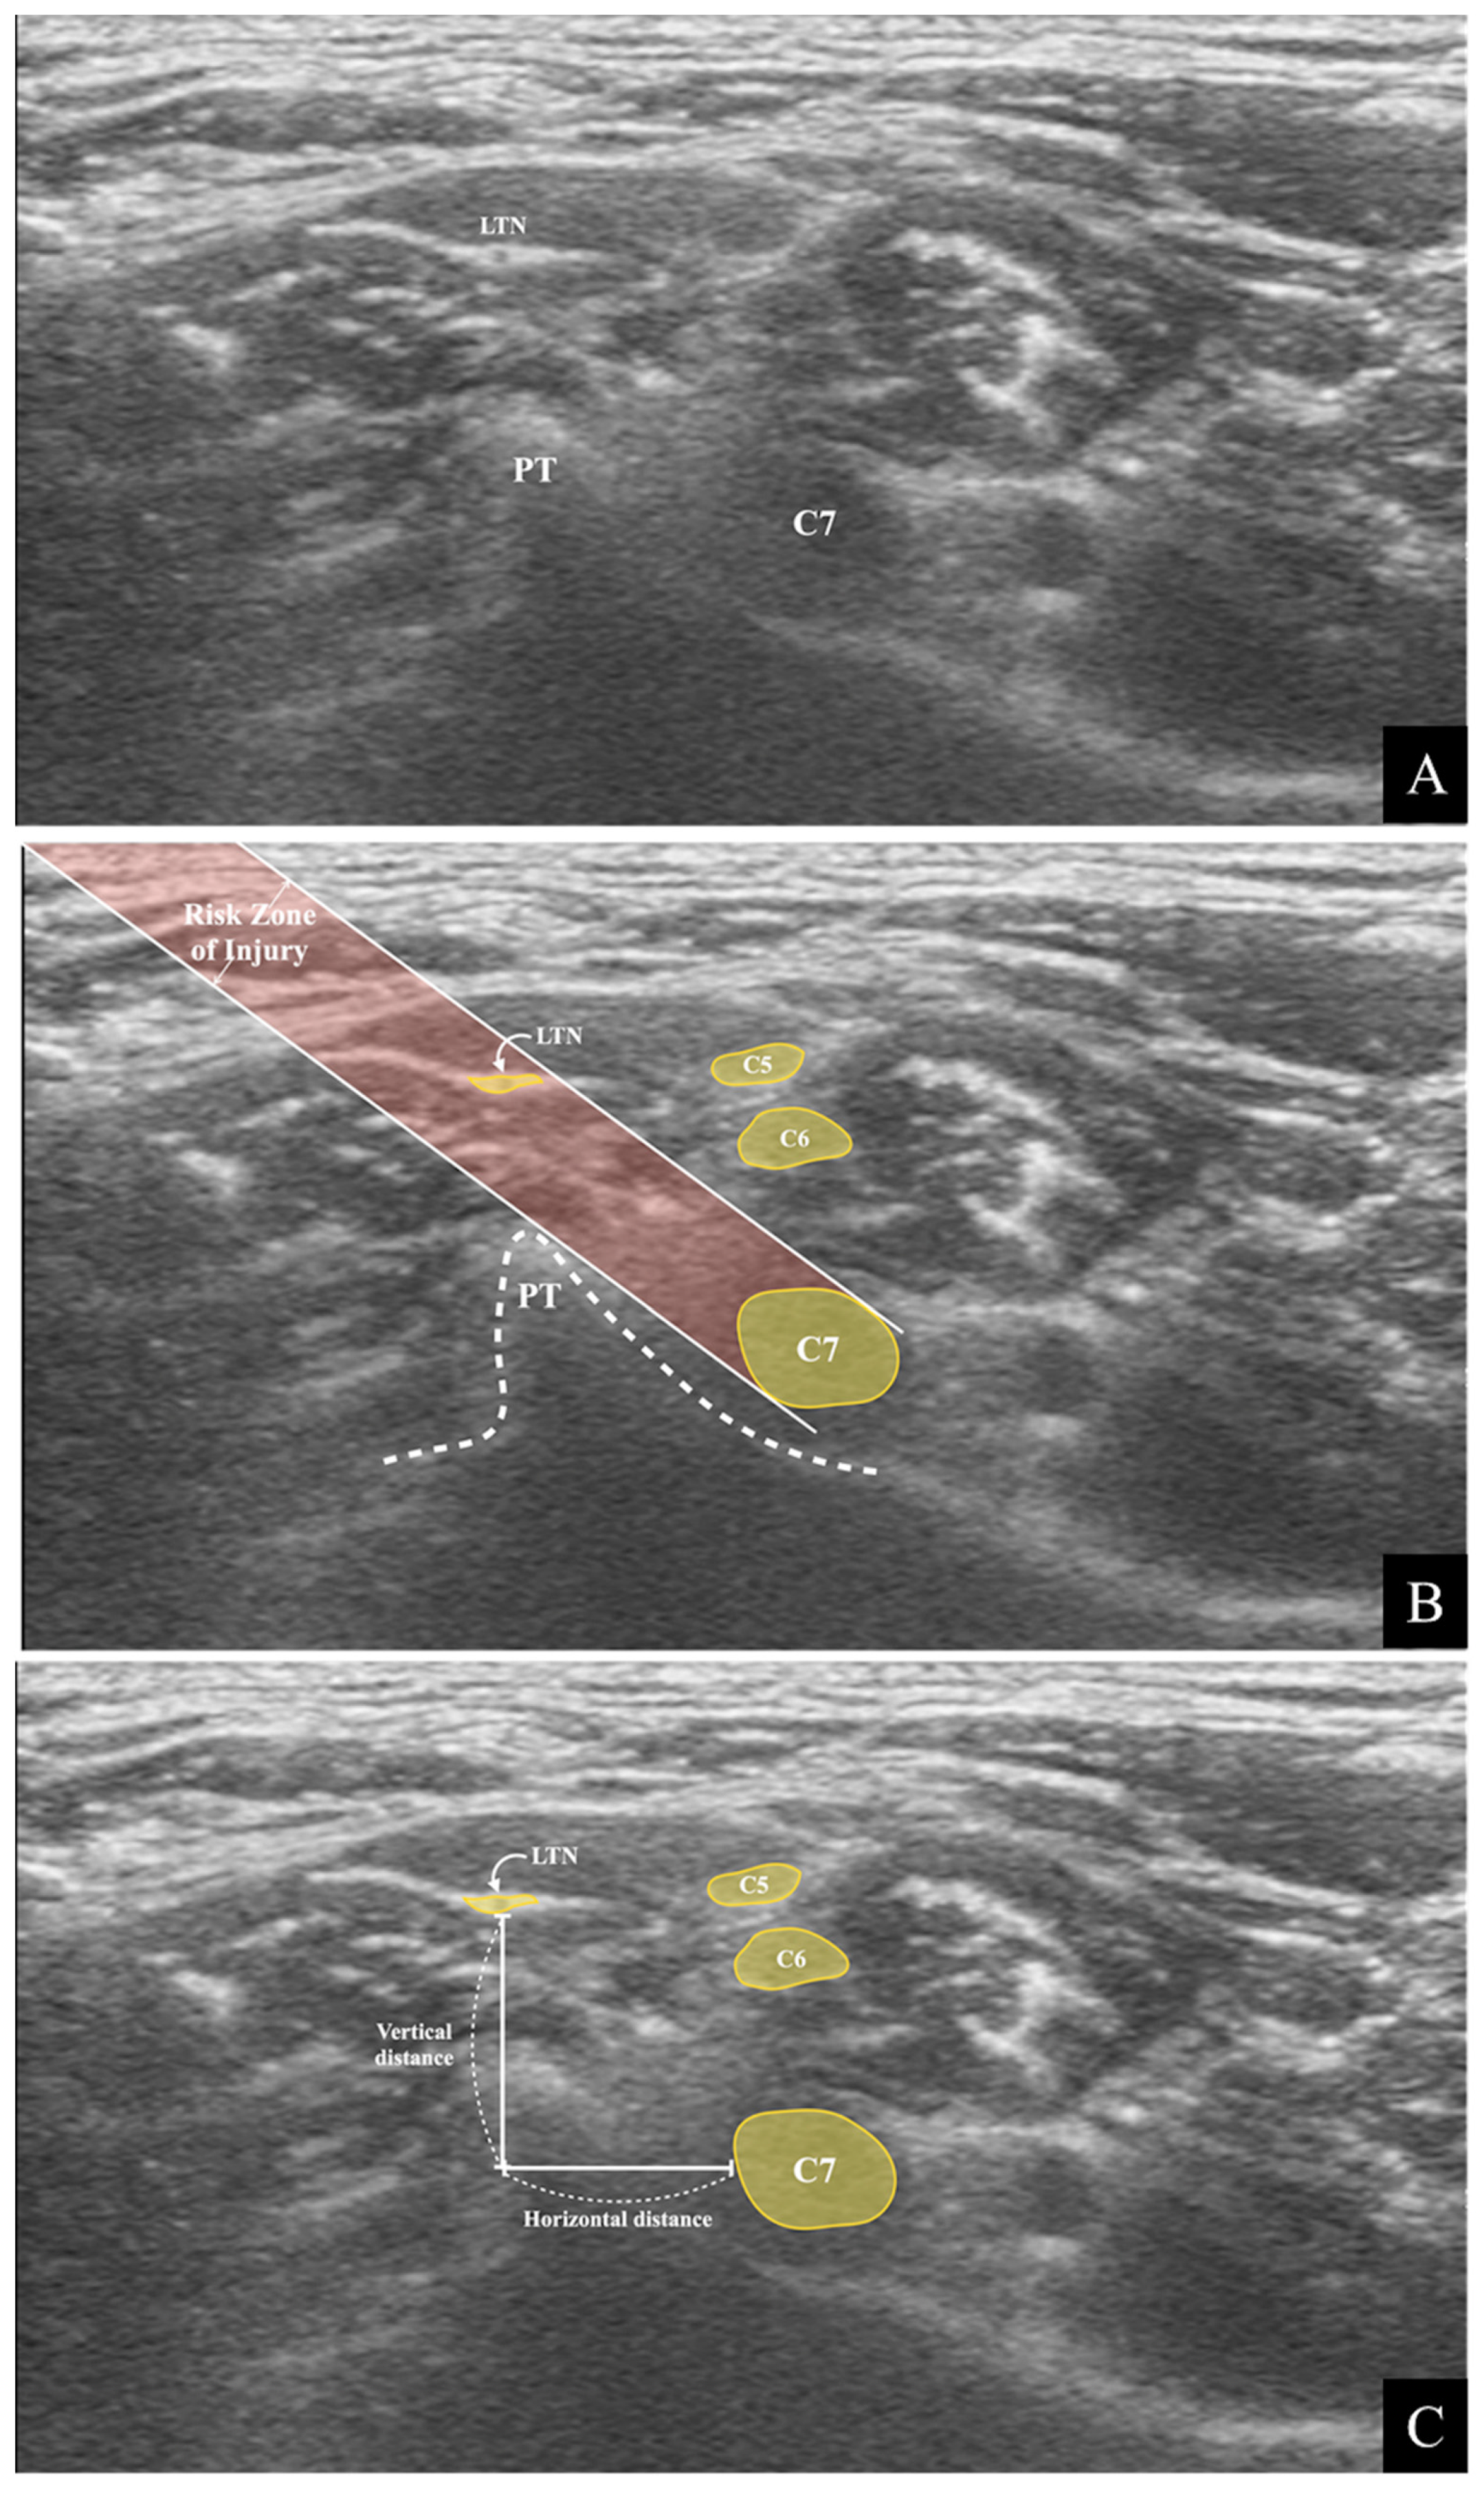

2.2. Simulated Risk Analysis of Long Thoracic Nerve Injury

- (1)

- A straight oblique line starting from the skin, passing through the tip of the posterior tubercle, and reaching the posteroinferior rim of the C7 nerve root.

- (2)

- A line parallel to line (1), starting from the skin and connecting to the superior margin of the C7 nerve root.

indicates that it was outside the risk area in the simulated risk analysis. The LTN’s mean location and locational area estimated by the mean ± standard deviation (SD) are presented. The painted area indicates that the needle’s trajectory is expected to be associated with a high risk of LTN injury.